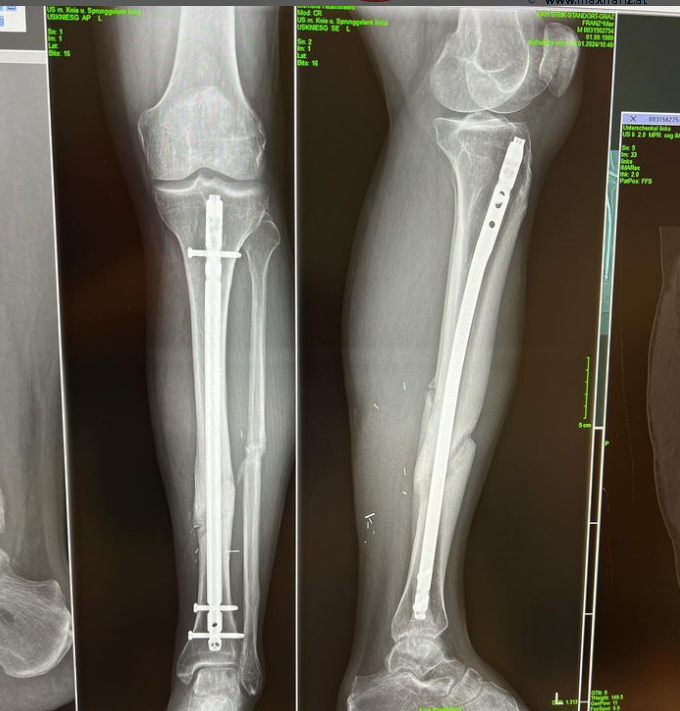

34-летний Макс Франц пока не хочет и слышать о завершении карьеры. Несмотря на разрыв крестообразной связки и раздробленные кости обеих ног. Франц серьезно упал 13 ноября 2022 года во время тренировки по скоростному спуску в Коппер-Маунтин (штат Колорадо) и получил открытый перелом левой голени, включая разрыв нерва, сложный перелом правой лодыжки и порез правой руки.

Была проведена успешная анатомическая реконструкция правого голеностопного сустава. Но повреждение нерва особенно затрудняет его возвращение. Заживление требует времени, много времени.

41 день после операции